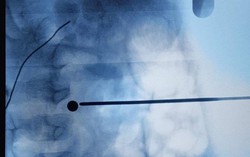

Cứu sống bé gái 10 tháng tuổi bị thủng thực quản cực kỳ nguy kịch

Phòng & chữa bệnh 16:29 04/08/2018Bé gái 10 tháng tuổi ở An Giang nguy kịch do bị thủng thực quản, tràn mủ màng phổ đã được các bác sĩ phẫu thuật cứu sống.